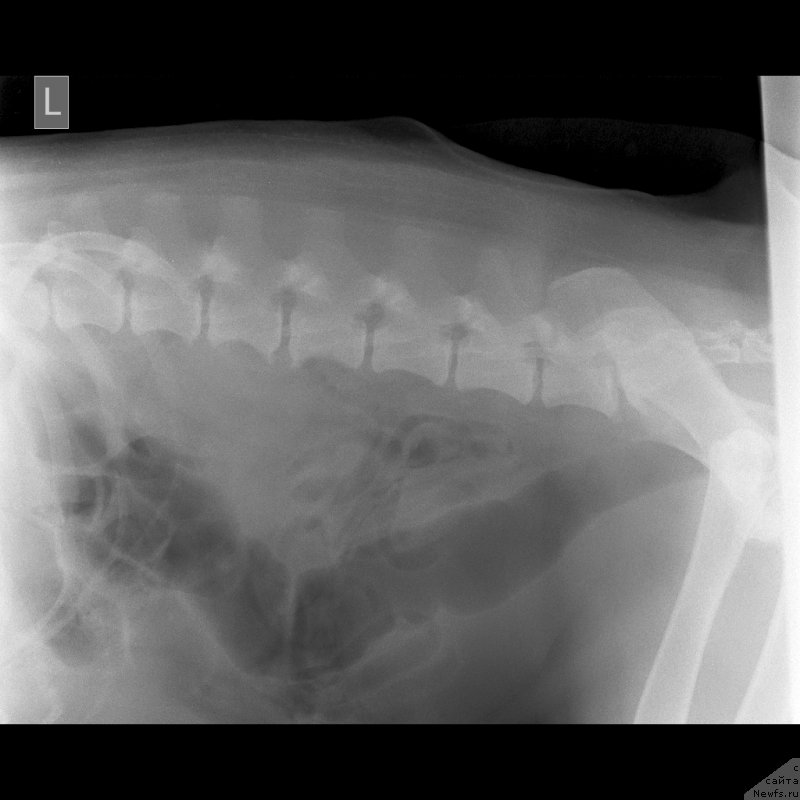

Второй ветеринар сделал ренген, где ничего не видно кроме начинающегося артроза.Опасения что слопал кость-отмели.

Сделали цифровой рентген в соседнем городе(Темиртау).Сейчас постараюсь его выставить.На мой взгляд не очень удачный.завтра наверное переделаем.

Второй ветеринар сделал ренген, где ничего не видно кроме начинающегося артроза.Опасения что слопал кость-отмели.

Сделали цифровой рентген в соседнем городе(Темиртау).Сейчас постараюсь его выставить.На мой взгляд не очень удачный.завтра наверное переделаем.

По клинической картине и по снимкам - спондилёз поясничного отдела позвоночника. Лечение: первые сутки дексаметазон 4 мг 3 раза /день или преднизолон, можно внутримышечно, и римадил 100мг 3 раза в день.